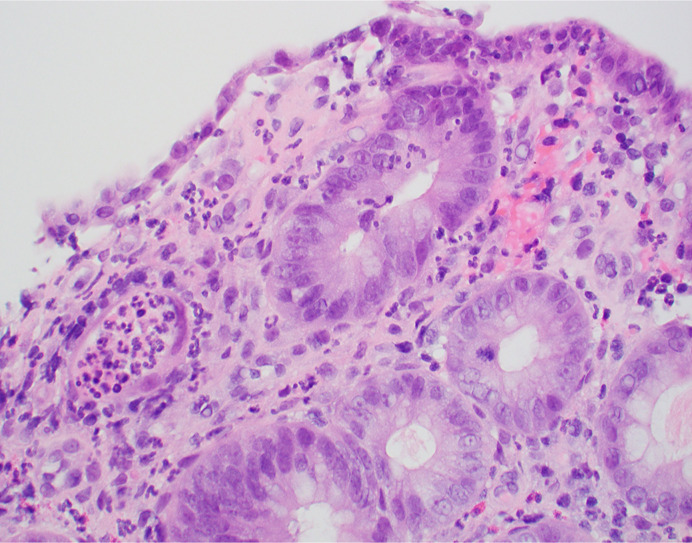

Introduction: Aseptic hepatic abscesses are a highly uncommon phenomenon and even more rare in the spectrum of extraintestinal manifestations of inflammatory bowel disease. Part of the spectrum of "neutrophilic disease," both the pathogenesis and the optimal management of these aseptic abscesses remain unclear. In the context of inflammatory bowel disease, sometimes these abscesses appear despite normal endoscopic findings.

Case presentation: We describe a highly uncommon case of aseptic hepatic abscess formation in a patient with inflammatory bowel disease.

Abstract Image